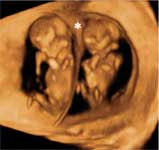

Hoy, por las técnicas de FIV, el número de gemelos o mellizos, o incluso trillizos, que nacen ha aumentado. Los embarazos múltiples, es decir cuando dentro del útero materno crecen dos o más bebés, tienen sus propias peculiaridades. Descubre cómo tienes que cuidarte en estos casos, los controles médicos que deberás seguir y comprueba con las ecografías cómo se desarrollan los bebés.